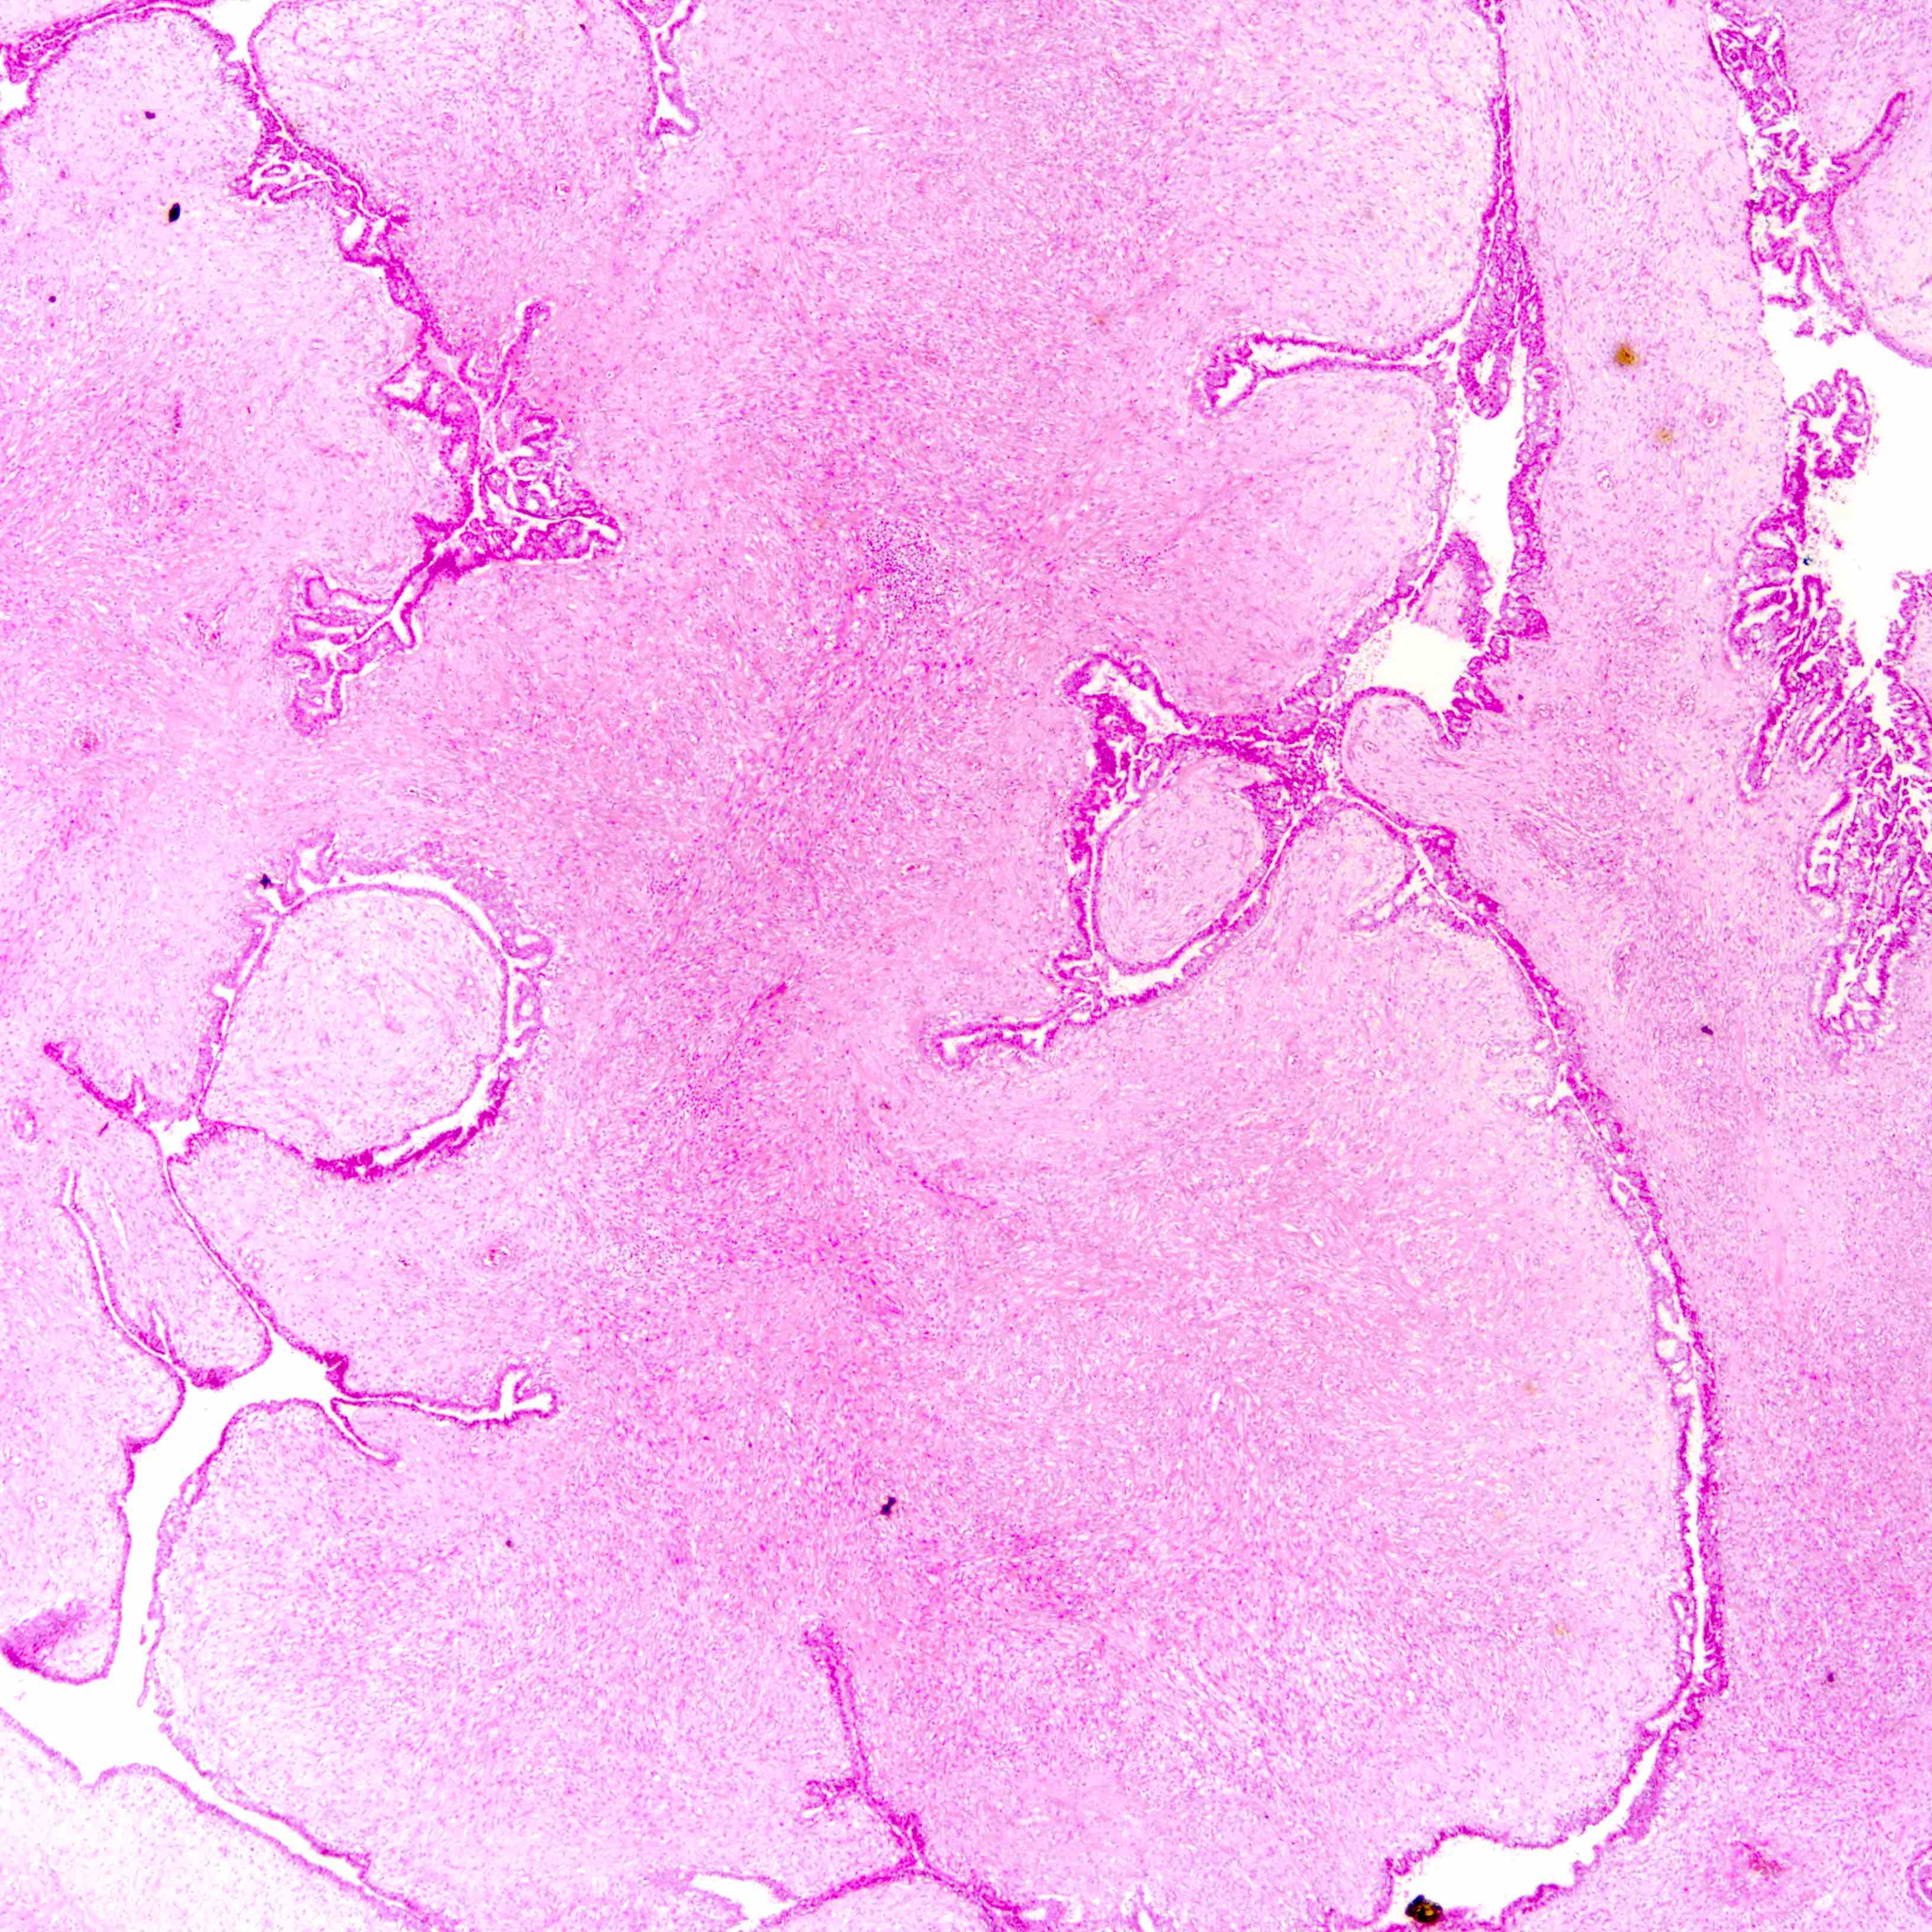

Microscopic (histologic) description

- Leaf-like (phyllodal) epithelial pattern formed by an exaggerated intracanalicular pattern

- Subepithelial condensation with increased stromal cellularity adjacent to epithelium

Microscopic (histologic) images

Contributed by Joshua J.X. Li, M.B.Ch.B. and Gary M. Tse, M.B.B.S.

Benign phyllodes tumor

Borderline phyllodes tumor

Malignant phyllodes tumor